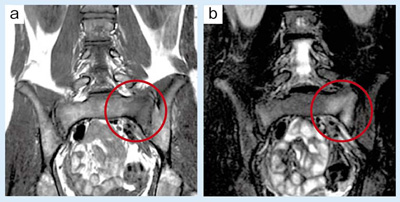

15歳,男性。若年性腰痛のルーチン検査で特に問題が認められない場合は,T1強調像(a)とFat SatのT2強調像のコロナル像(b)を追加することで,仙骨の疲労骨折が見つかる場合がある。

a:T1WI,COR,FOV:300mm,TR/TE:450/11,FA:90°,スライス厚:3mm

b:Fat Sat T2WI,COR,FOV:300mm,TR/TE:2440/90,FA:90°,スライス厚:3mm